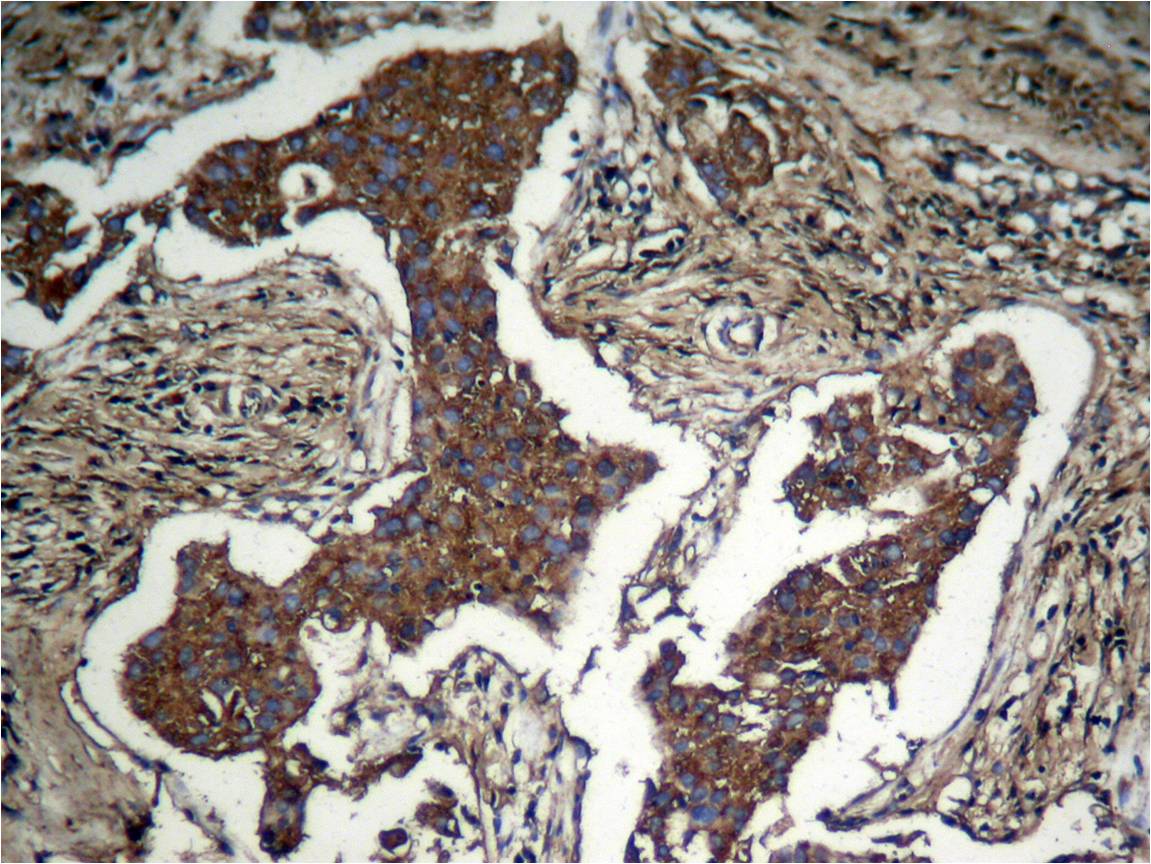

- Immunohistochemical analysis of paraffin-embedded human breast carcinoma tissue using Akt(Phospho-Ser473) Antibody P40054(left) or the same antibody preincubated with blocking peptide(right).

- Immunohistochemical analysis of paraffinembeddedhuman Lung carcinoma tissue usingAkt (Phospho-Ser473) Antibody P40054.